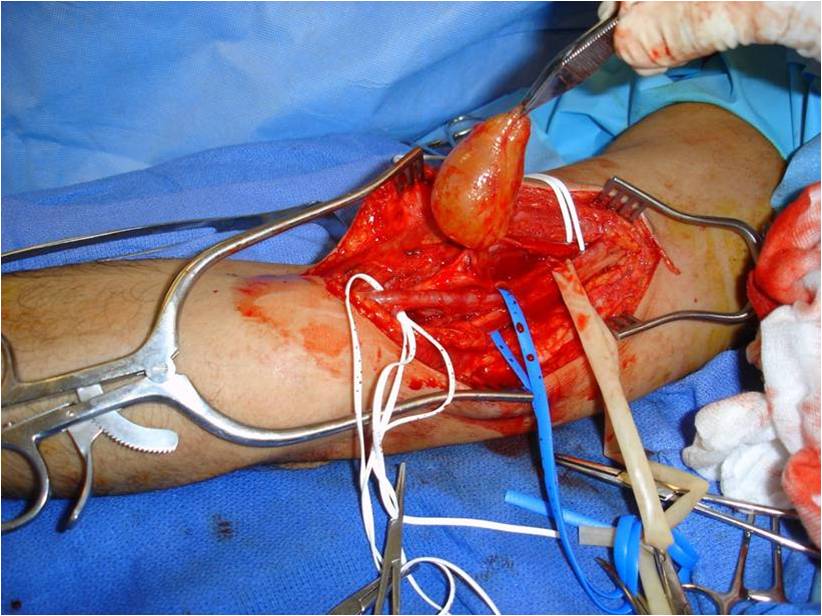

Treatment

• Surgical Excision (Fig. 9, 10, 11)

o Marginal Excision; Spare nerve from excision

The epineurium is opened carefully on a side opposite nerve fascicles and the mass is gently separated from the nerve fascicles and epineurium.

o Rarely if ever recurs

Fig. 9-11 Intraoperative photographs demonstrate medial approach to the arm and neurovascular dissection, including; median nerve and brachial artery. Schwannoma is easily distinguished in the median nerve. The sheath of the nerve is opened on the opposite side of the splayed out nerve fascicles and the tumor removed. The nerve was spared.